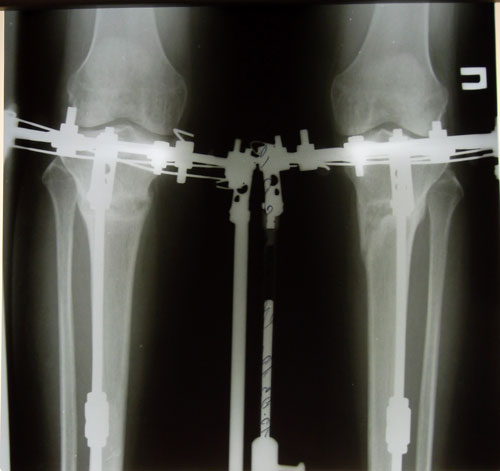

30 дней с момента операции.

РЕНТГЕН НА 30 - ЫЙ ДЕНЬ С МОМЕНТА ОПЕРАЦИИ.

РЕНТГЕН ДО ОПЕРАЦИИ